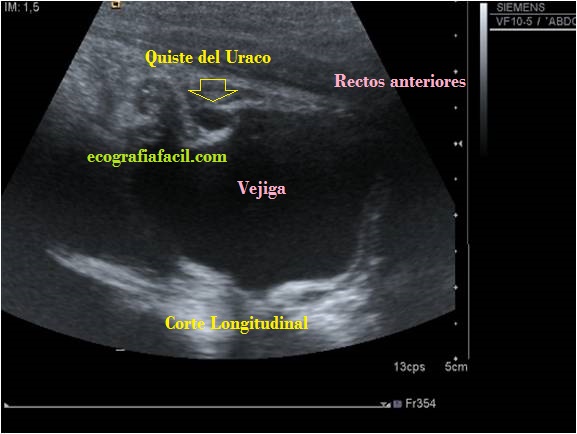

Nos quedamos con el número 2 y te lo presento en imágenes…mira:

La paciente acude por molestias abdominales, la prueba discurre normalmente, pero al pasar en línea media antes de llegar a la vejiga, una imagen pequeña, ovalada, medial, anecoica ocupa la parte superior de la vejiga. Se demuestra en la primera imagen, se corrobora con la imagen 2, o corte longitudinal donde se demuestra clarísimamente su situación anatómica con respecto a la vejiga y a los tejidos circundantes.

El doppler no aportó información adicional, la radióloga informó «Quiste del Uraco». Estoy seguro que si alguna vez lo ves, te vas a acordar de este Post…

Para este estudio te recomiendo encarecidamente frecuencias altas en el ancho de banda de tu sonda, si puedes llegar a usar la lineal, hazlo.